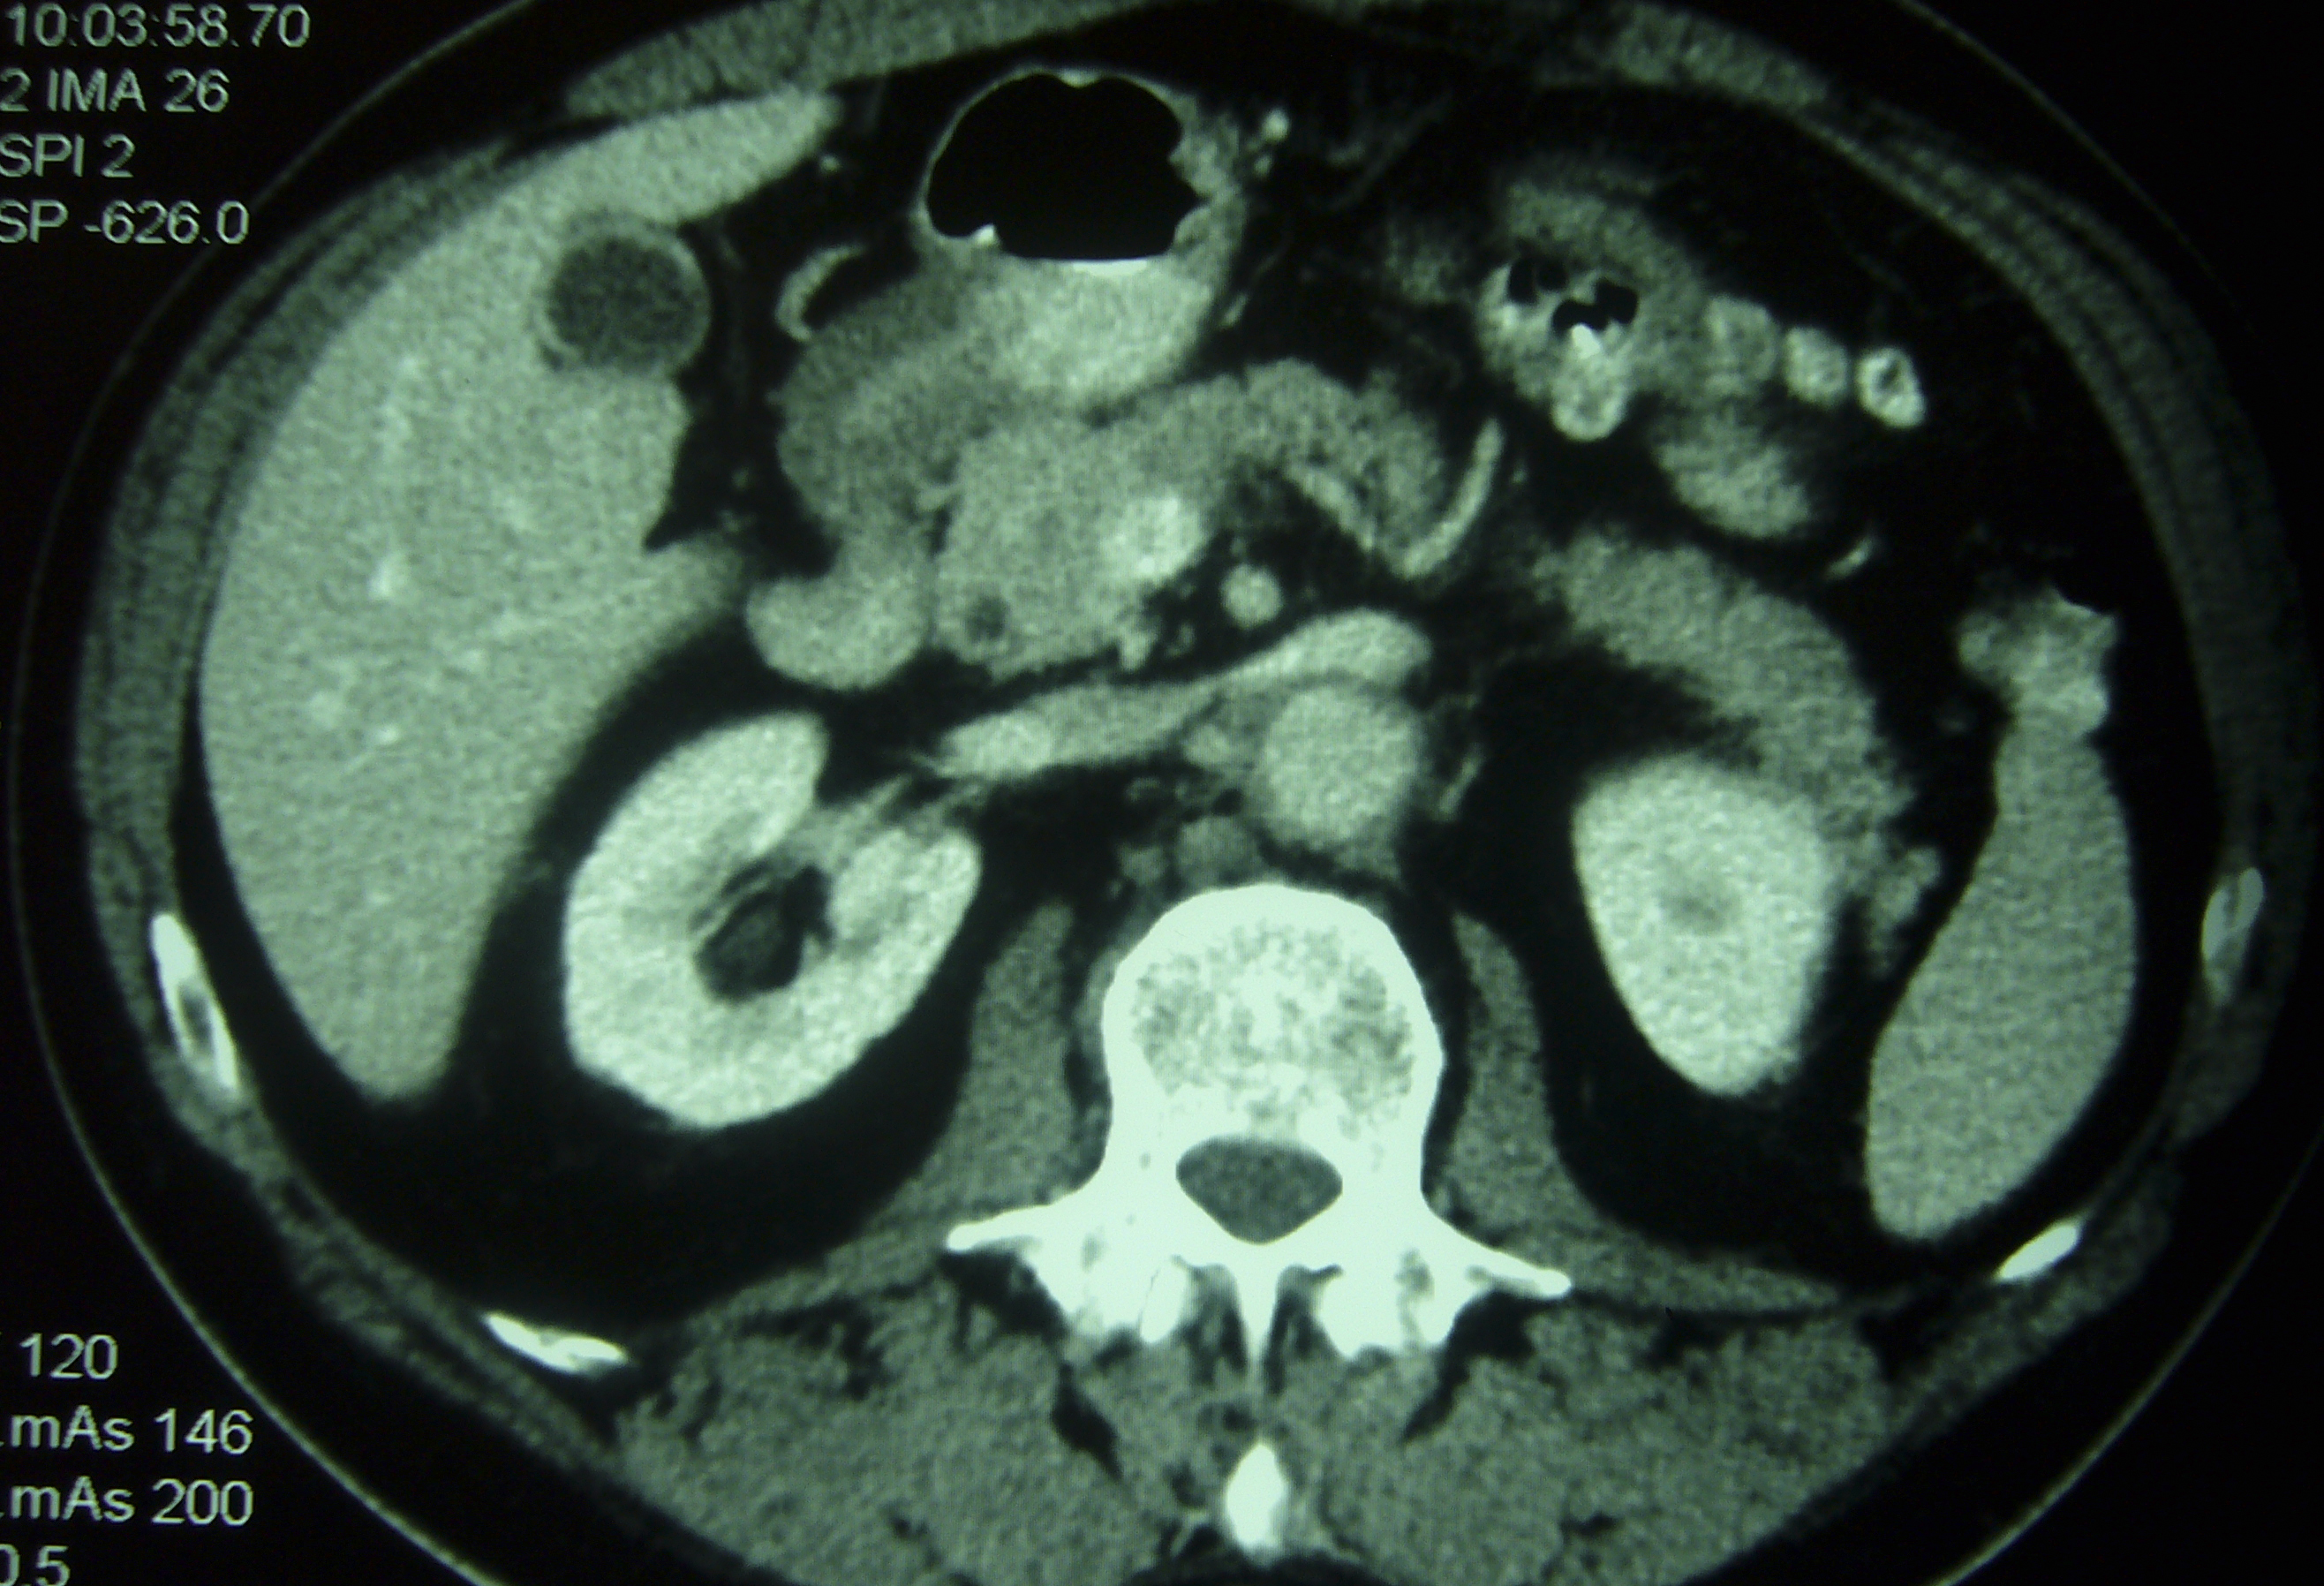

We present the case of a male patient with post traumatic retroperitoneal fibrosis whose main clinical expression was low-back pain. Diagnosis was established using CAT-scan and MRI, which revealed a large mass of soft tissue that almost entirely enveloped the abdominal aorta. Treatment with 40 mg of prednisone every 24 hours was established. This dose was reduced gradually, and progressive remission of clinical signs and symptoms was achieved, with a significant improvement of subsequent imaging-test results. Treatment was continued for one year. Two and a half years later the patient remains symptom-free, with no recurrence of his condition.Descargas